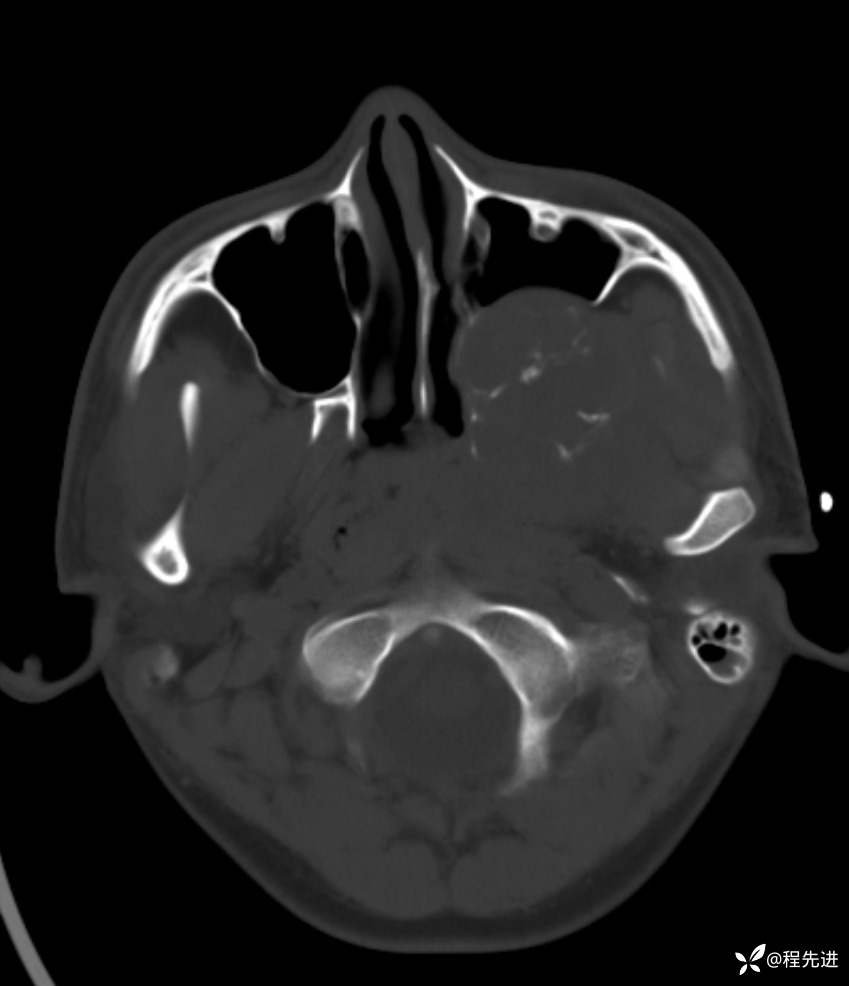

简要病史:左眼视力下降20余天,伴肿胀疼痛不适半月

CT平扫:

骨窗: